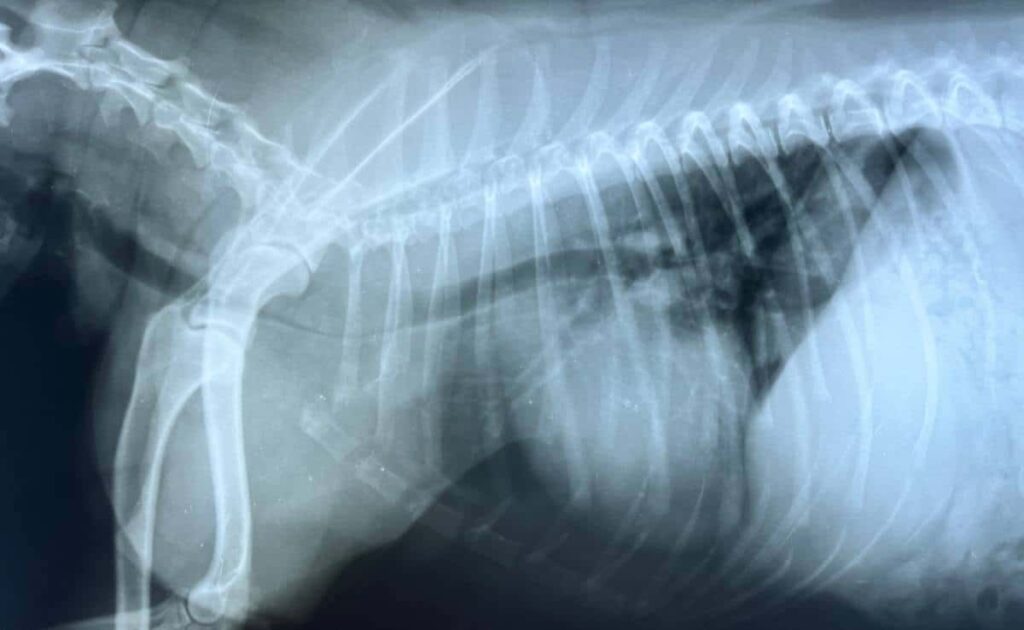

Tracheal Collapse With Axial Rotation . Both entities are collectively referred to as expiratory central airway collapse (ecac). tracheal collapse with axial rotation was diagnosed in four dogs. tracheobronchomalacia (tbm) and excessive dynamic airway collapse (edac) are airway abnormalities that share a common feature of expiratory narrowing but are distinct pathophysiologic entities. tracheal collapse is a weakness of the tracheal wall leading to expiratory central airway collapse of more than 50% compared to inspiration. tracheomalacia, or sometimes described as tracheobronchomalacia, is a common incidental finding on imaging of the chest of. tracheobronchomalacia (tbm) and excessive dynamic airway collapse (edac) are diseases that are. expiratory central airway collapse is an underdiagnosed disorder that can coexist with and mimic asthma, chronic obstructive pulmonary disease, and bronchiectasis. excessive tracheal collapse is characterized by flaccidity of the tracheal. Awareness of expiratory central airway collapse and its spectrum of symptoms is paramount to its recognition. Radiographs showed increased tracheal dorsoventral height at.

Tracheal Injury StatPearls NCBI Bookshelf Tracheal Collapse With Axial Rotation Radiographs showed increased tracheal dorsoventral height at. tracheal collapse with axial rotation was diagnosed in four dogs. tracheobronchomalacia (tbm) and excessive dynamic airway collapse (edac) are diseases that are. excessive tracheal collapse is characterized by flaccidity of the tracheal. Awareness of expiratory central airway collapse and its spectrum of symptoms is paramount to its recognition. Both entities. Tracheal Collapse With Axial Rotation.

Tracheomalacia Causes, Symptoms & Treatment Tracheal Collapse With Axial Rotation Radiographs showed increased tracheal dorsoventral height at. tracheal collapse with axial rotation was diagnosed in four dogs. expiratory central airway collapse is an underdiagnosed disorder that can coexist with and mimic asthma, chronic obstructive pulmonary disease, and bronchiectasis. tracheal collapse is a weakness of the tracheal wall leading to expiratory central airway collapse of more than 50%. Tracheal Collapse With Axial Rotation.

Lateral thoracic radiographs of dogs with endoluminal tracheal stent Tracheal Collapse With Axial Rotation tracheobronchomalacia (tbm) and excessive dynamic airway collapse (edac) are airway abnormalities that share a common feature of expiratory narrowing but are distinct pathophysiologic entities. expiratory central airway collapse is an underdiagnosed disorder that can coexist with and mimic asthma, chronic obstructive pulmonary disease, and bronchiectasis. Both entities are collectively referred to as expiratory central airway collapse (ecac). Awareness. Tracheal Collapse With Axial Rotation.